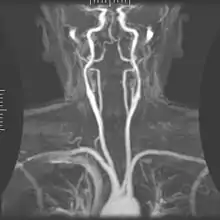

Magnetic resonance angiography

Magnetic resonance angiography (MRA) generates pictures of the arteries to evaluate them for stenosis (abnormal narrowing) or aneurysms (vessel wall dilatations, at risk of rupture). MRA is often used to evaluate the arteries of the neck and brain, the thoracic and abdominal aorta, the renal arteries, and the legs (called a "run-off"). A variety of techniques can be used to generate the pictures, such as administration of a paramagnetic contrast agent (gadolinium) or using a technique known as "flow-related enhancement" (e.g., 2D and 3D time-of-flight sequences), where most of the signal on an image is due to blood that recently moved into that plane (see also FLASH MRI).[35]

Techniques involving phase accumulation (known as phase contrast angiography) can also be used to generate flow velocity maps easily and accurately. Magnetic resonance venography (MRV) is a similar procedure that is used to image veins. In this method, the tissue is now excited inferiorly, while the signal is gathered in the plane immediately superior to the excitation plane—thus imaging the venous blood that recently moved from the excited plane.[36]